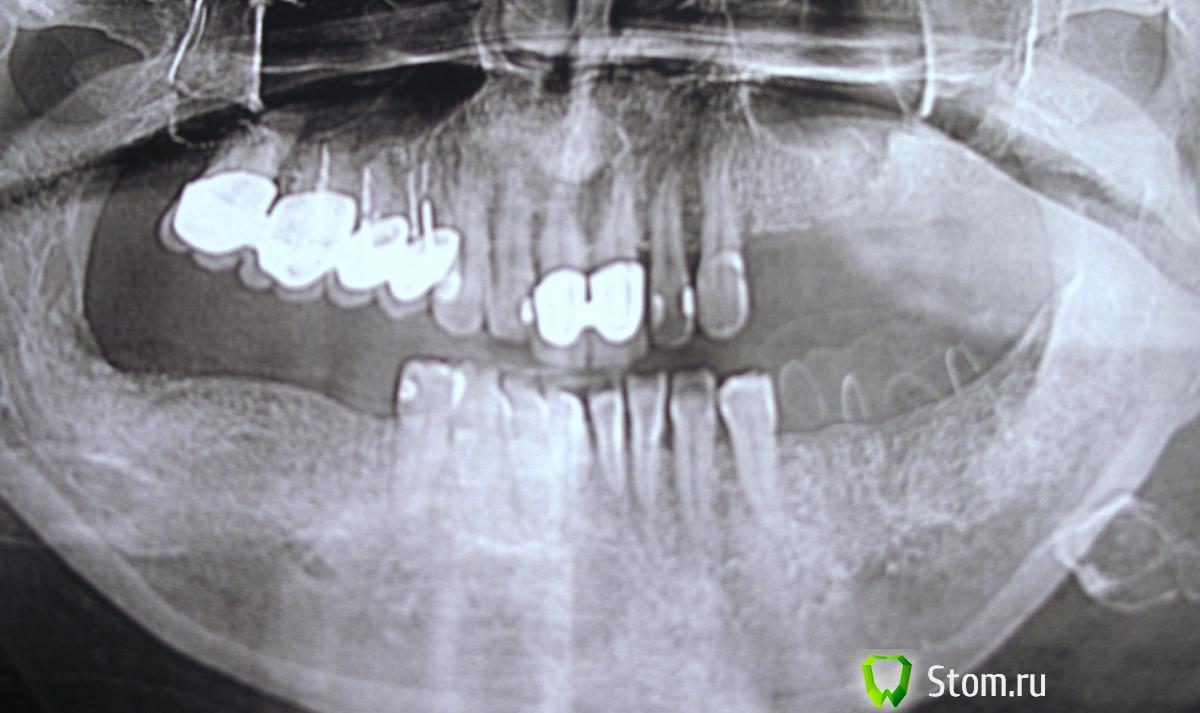

vladimird777 Опубликовано 9 апреля, 2012 Поделиться Опубликовано 9 апреля, 2012 Помогите начинающим пожалуйста!) Начинаем ставить импланты в частной середнячковой клинике Ростова, опыт только теоритический, сразу попалась большая работа так что не хочется попасть в просак)), Планирую установить импланты в области 34,35,37-сделать мост, справа аналогично, пока делаем только низ. Вопросы: верный выбор расположения имплантов, на что обратить особое внимание? как сделать хир. шаблон в условиях обычной зт. лаб.,система мис.На чем основывается выбор платформы? Буду очень признателен за любую инфу,пишите пожайлуста. орто прикладываю)) Ссылка на комментарий

Crossovok Опубликовано 9 апреля, 2012 Поделиться Опубликовано 9 апреля, 2012 орто прикладываю)) Ничего себе слой керамики на верхних резцах Ссылка на комментарий